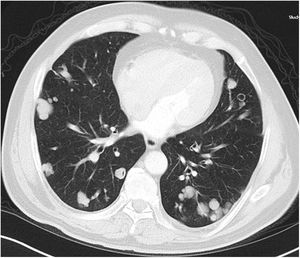

A relationship was identified between the pleura and one or more of the lesions in 25 of the 34 patients diagnosed with PAE (73.5%) (Fig. 1). Following the lesion-pleura relationship, multiple lesions were uniformly scattered throughout the bilateral lung parenchyma in 19 patients (55.8%), seven patients (20.6%) presented with a solitary pulmonary lesion and three patients (8.8%) had multiple unilateral lesions. The diameter of one or more lesions was greater than 3cm in 11 patients (32.4%), only three patients (8.8%) had conglomerated lesions (Fig. 2) and seven patients (20.6%) showed cavitization in some of the lesions. The majority of cavitary mass measured greater than 3cm (Fig. 3). Calcified lesions were recorded in five patients (14.7%), and some of the calcified lesions with lobulated contours had a typical popcorn appearance. Lobulated contours were observed in a significant proportion of non-calcified lesions. Some of the lesions had irregular contours and spicular extensions mimicking malignant processes in five patients (14.7%), while three patients (8.8%) showed multiple micronodular densities with a bilateral uniform dispersion pattern (Fig. 4). The appearance of pulmonary involvement resembled miliary tuberculosis. Parenchymal lesions were accompanied by pleural effusion and parenchymal consolidation in only three patients (8.8%) (Table 1).

Axial thoracic CT scan with lung parenchyma window of a 74-year-old male patient showing multiple lesions in the bilateral lung parenchyma. Some of the lesions show a tendency to cavitization and some show a tendency to conglomeration. Parenchymal lesions tend to have peri-pleural localization in the lung periphery. The patient has been followed for 6 years due to PAE.